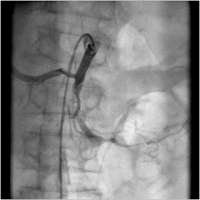

Embolus - Passage

Abbildung 3: Versuch der Passage des Embolus mittels Doppeldrahttechnik ("intermediate" Draht, Asahi-Miraclebros 4,5 g)

Keywords:

Angiographie

,

Doppeldrahttechnik

Embolus

Gefäßmedizin